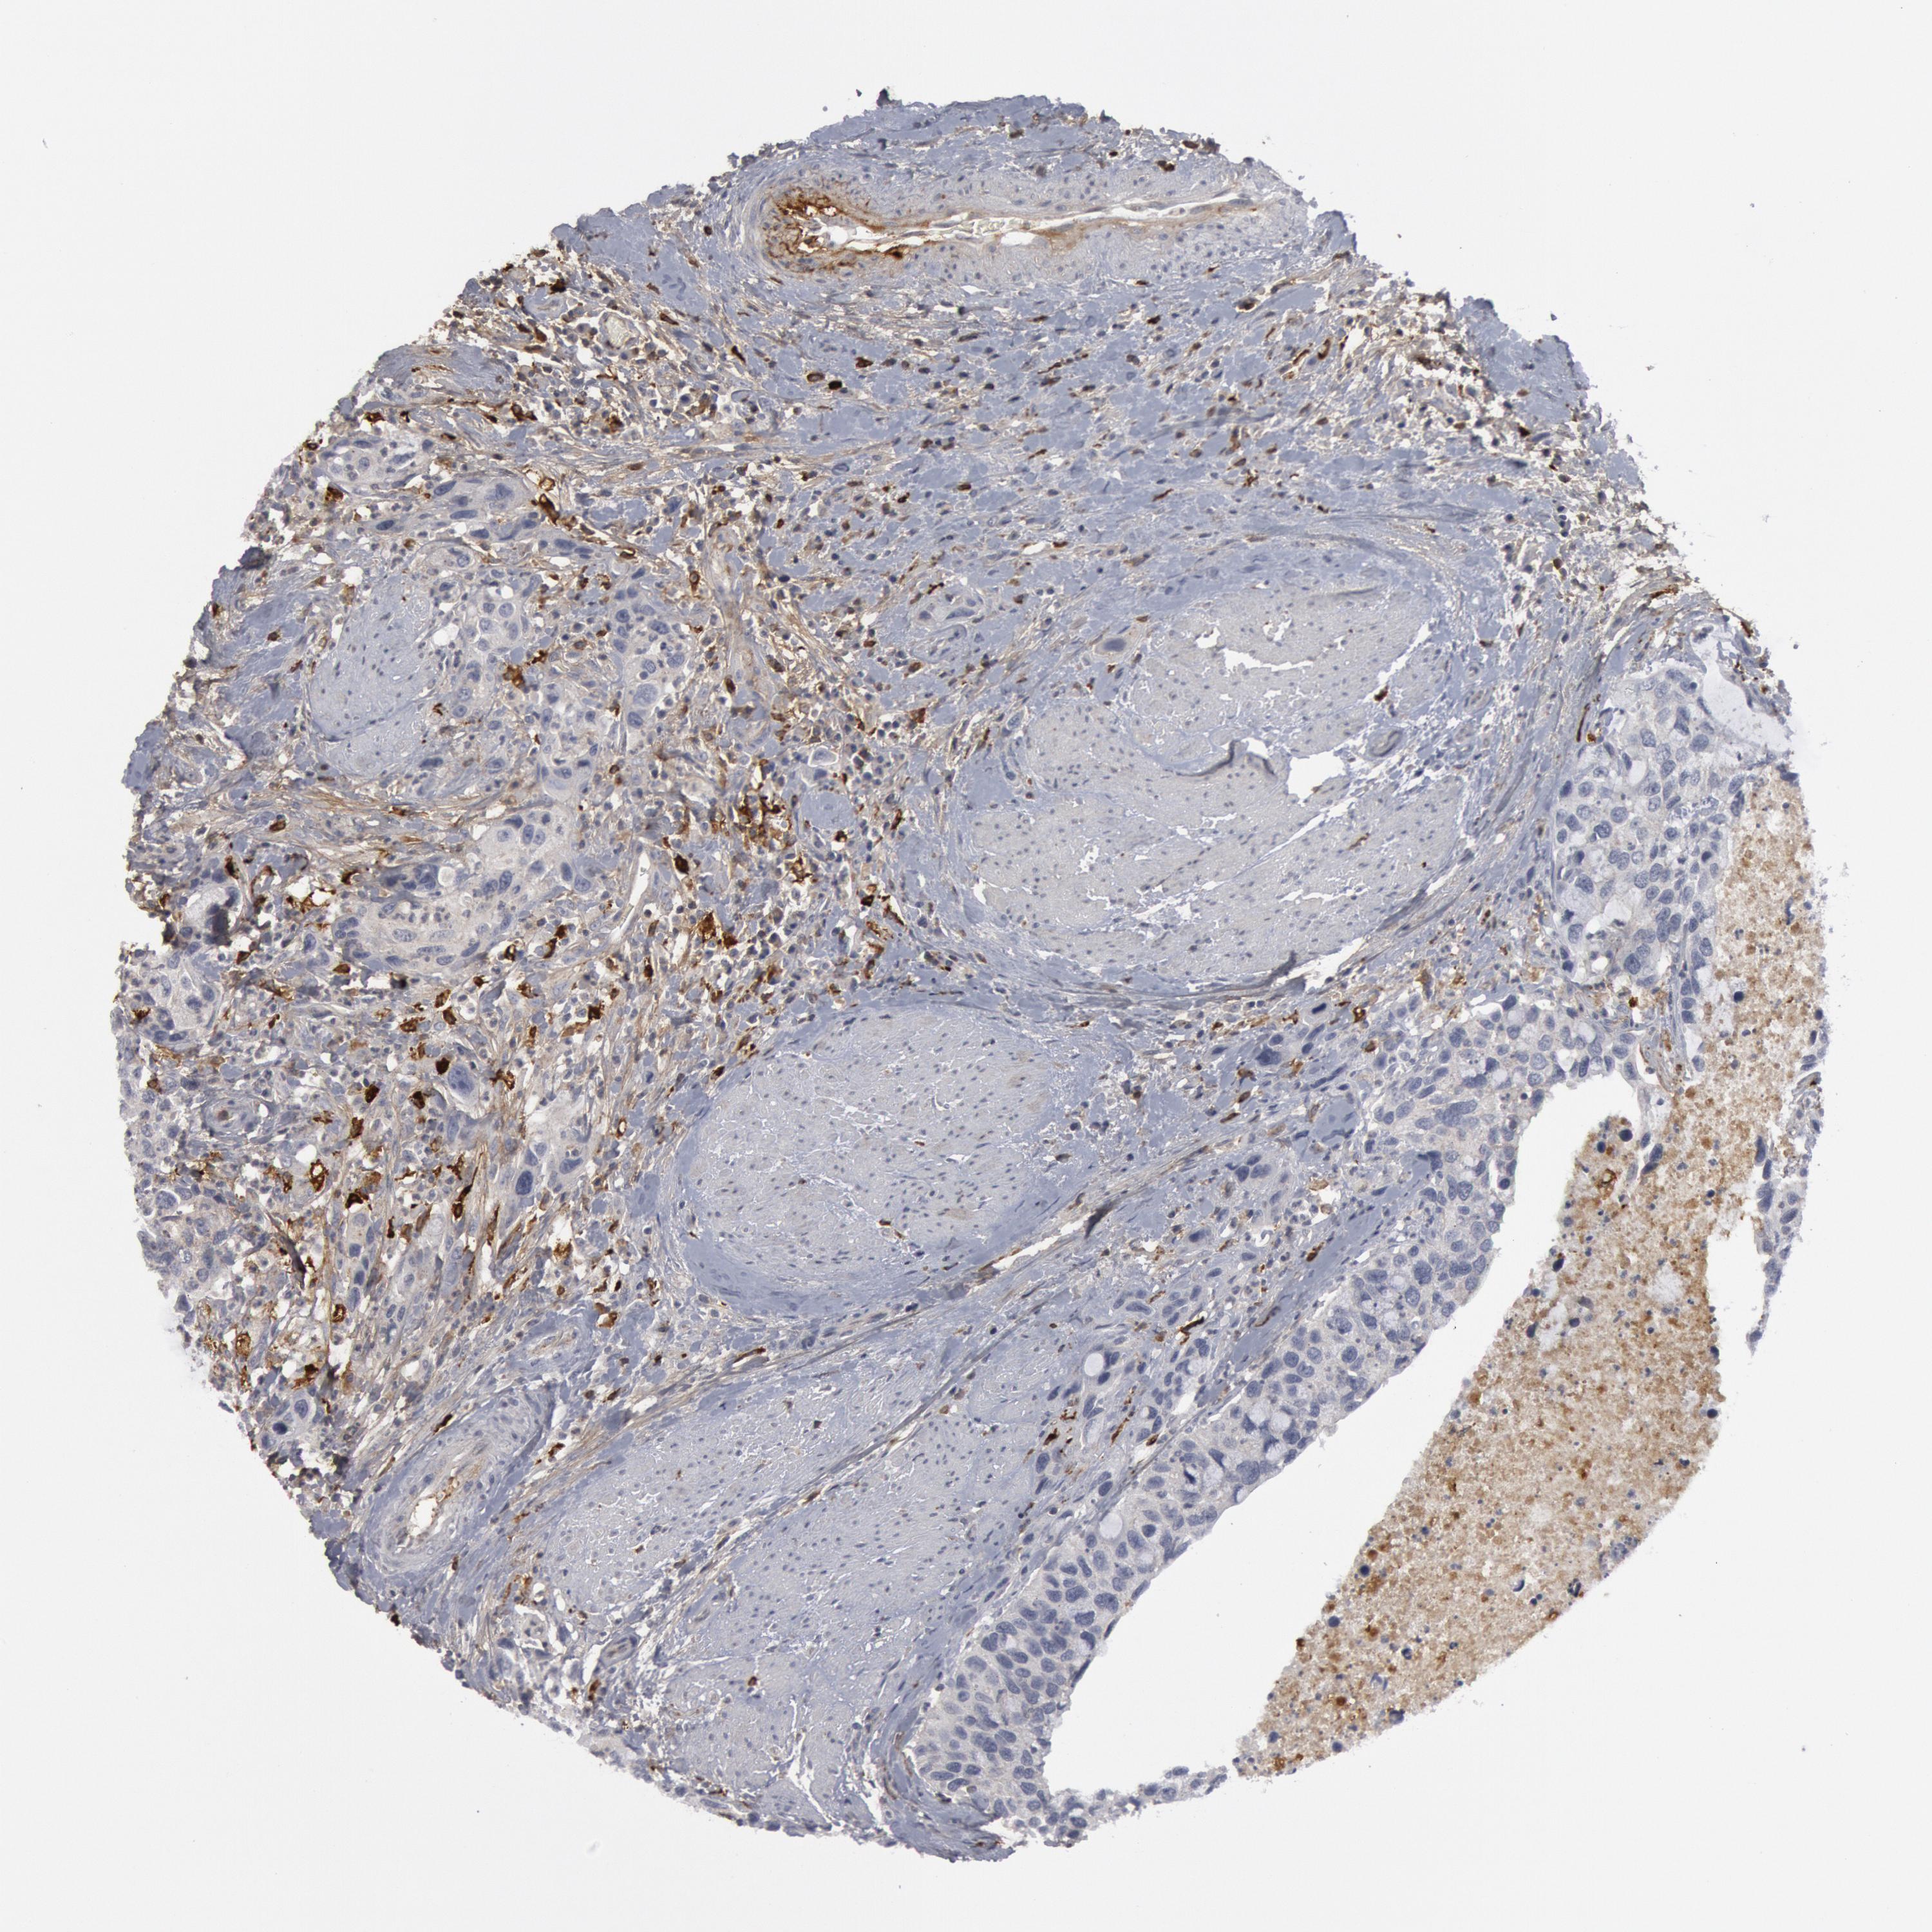

UROTHELIAL CANCER - Protein expressioni

A mouse-over function shows sample information and annotation data. Click on an image to view it in a full screen mode. Samples can be filtered based on level of antibody staining by selecting one or several of the following categories: high, medium, low and not detected. The assay and annotation is described here.

Note that samples used for immunohistochemistry by the Human Protein Atlas do not correspond to samples in the TCGA dataset.

Antibody stainingi

Antibody staining in the annotated cell types in the current human tissue is reported as not detected, low, medium, or high, based on conventional immunohistochemistry profiling in selected tissues. This score is based on the combination of the staining intensity and fraction of stained cells.

Each image is clickable and will lead to virtual microscopy that enables deeper exploration of all samples and also displays staining intensity scores, fraction scores and subcellular localization as well as patient and tissue information for each sample.

Antibody HPA001471

Antibody CAB009828

Staining

High

Medium

Low

Not detected

Intensity

Strong

Moderate

Weak

Negative

Quantity

>75%

75%-25%

<25%

None

Location

Nuclear

Cytoplasmic/membranous

Cytoplasmic/membranous,nuclear

Urothelial carcinoma, High grade

Urothelial carcinoma, Low grade

Adenocarcinoma, NOS